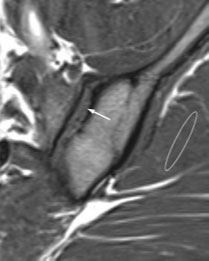

Un signal IRM anormal dans l’interligne sacro-iliaque : un nouveau signe diagnostique de spondyloarthrite ?

Pr Thao Pham CHU Sainte-Marguerite - Marseille

L’IRM des sacro-iliaques a pris une part importante dans les critères diagnostiques des spondyloarthrites. Selon l’ASAS, le diagnostic de sacro-iliite repose sur la seule présence d’œdème médullaire en « quantité suffisante ». Cependant, il existe d’autres anomalies telles que les enthésites, l’épanchement articulaire, les érosions, etc. Selon les recommandations...